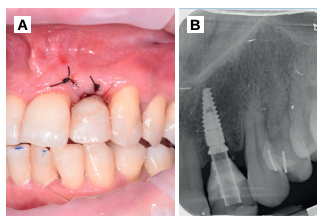

Transcurrida una semana, se procedió a la retirada de la sutura, observando una buena cicatrización de los tejidos blandos (Figura 9).

Tras 3 meses de la colocación del implante, se realizó la segunda fase, mediante una incisión horizontal palatinizada, para desplazar el tejido en una dirección vestibular (Figura 10). Se pudo apreciar el aspecto homogéneo del injerto de dentina, en contacto con el pilar de titanio (Figura 11), que fue rebasado con acrílico para la colocación de una corona provisional (Figuras 11 y 12). A la semana de la segunda fase, se valoró el aspecto del tejido gingival y la óptima ganancia de tejido a nivel horizontal (Figura 13).

palatinizada.

de titanio para rebasar y confección de corona de resina

provisional (B-D).

post-operatorio inmediato.